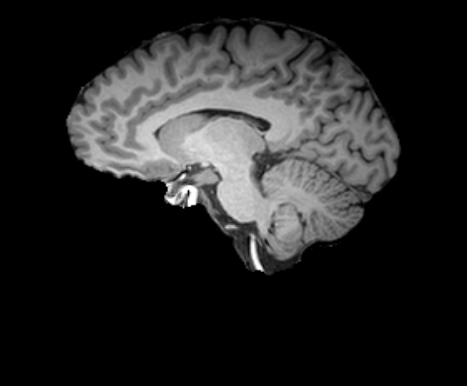

3.2.2 Robustness

In this experiment, we evaluate the robustness of Polaffini and the competing methods by computing a failure rate. We considered as potential outliers all cases for which the average Dice score over all regions after registration was below 0.34 (Z-score below -1.5, pooling Dices from all affine methods). All potential outliers were visually inspected to assess the reason behind the poor anatomical structure overlap score. All of them were clear failure cases, not just a residual misalignment to be expected after an affine registration. The failure counts for each method are reported in table 2. Almost all of the failure cases only occurred when registering with Flirt, mostly when subjects from the IXI dataset were involved. The most common failure type, showcased in Fig 6-a., consists of a local minimum where the frontal part of the moving brain is matched with the cerebellum of the reference one, a less frequent upside-down outcome is showcased in Fig 6-b. We suspect it is due to the fact that images from IXI have their axes ordered differently compared to the other two datasets and the template. However, since this information is contained in the header, it is unclear why Flirt could not handle the situation properly. Without the restriction of the angle search to , Flirt would give worse results (19 failure cases for subject-to-template and 61 for subject-to-subject). The only failure case using Anima for subject-to-subject is shown in Fig 6-c. For the rest of this section, we discard registrations if at least one of the methods has failed.

| reference | moving | moved | reference and moved | |

| a. | ukb_1154012-20252 | adni_AD-012-S-0720 | registered with Flirt | |

![]() |

|

| b. | ixi_165-HH-1589 | ukb_1145033-20252 | registered with Flirt | |

| c. | ixi_143-Guys-0785 | adni_MCI-003-S-6258 | registered with Anima-aff | |